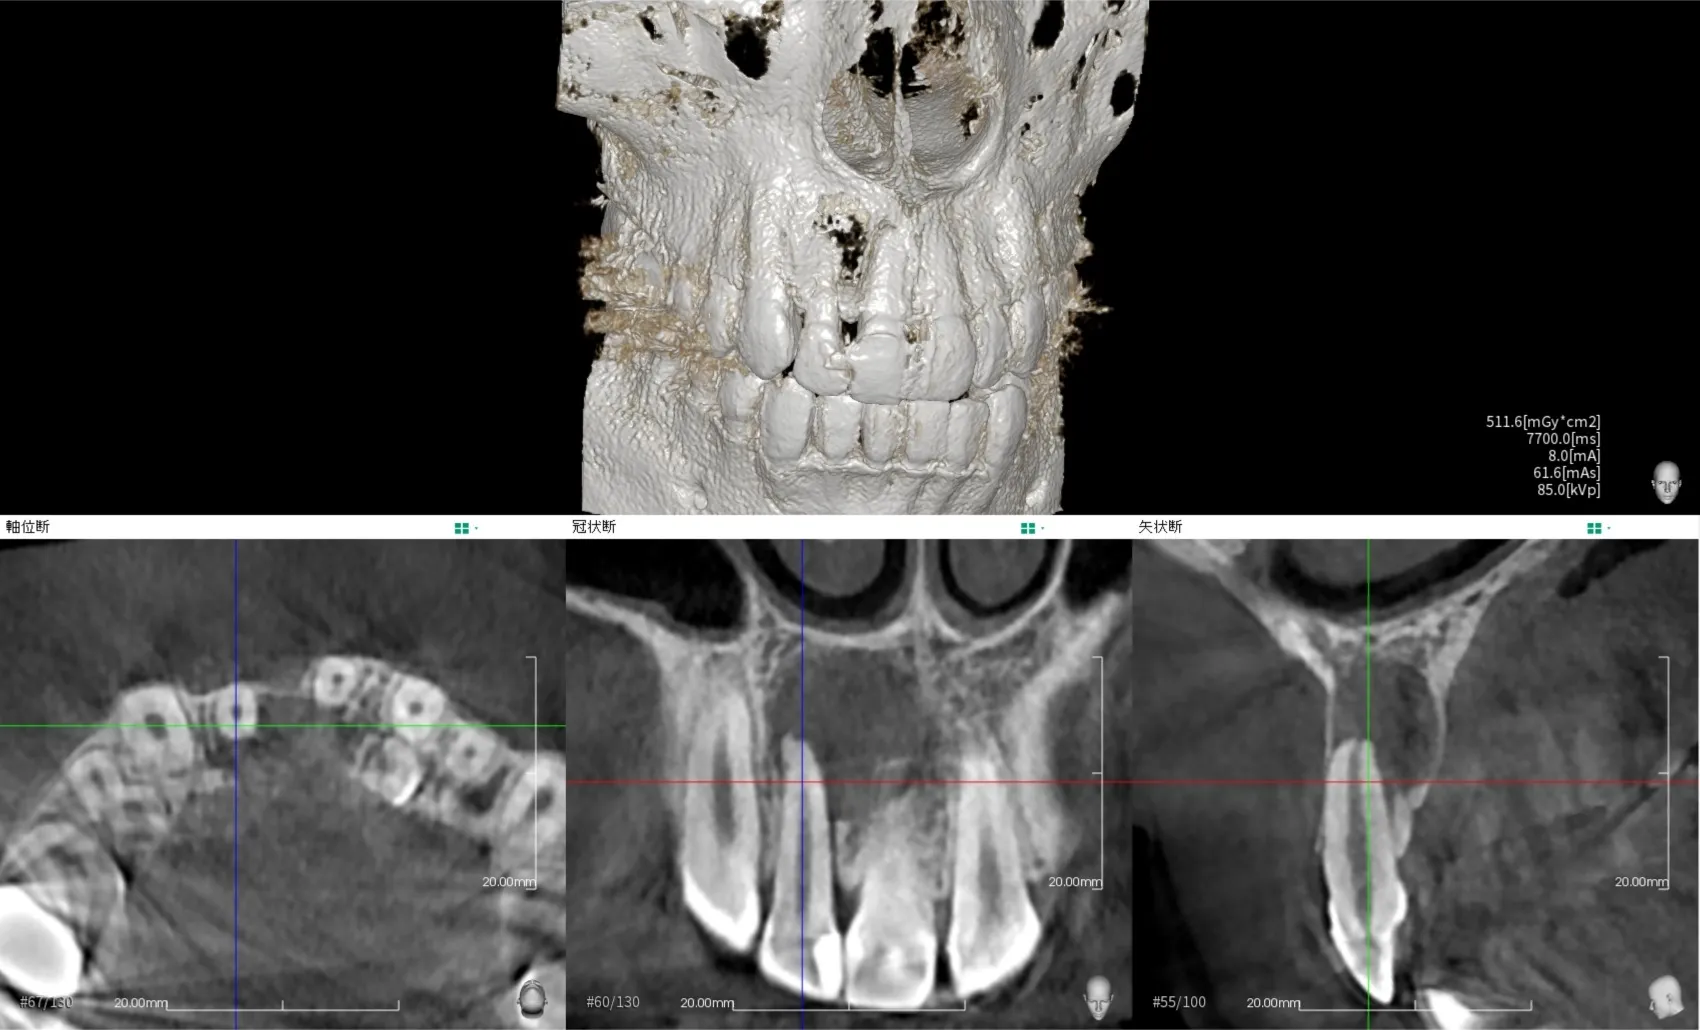

巨大な歯根膿瘍の根管治療1.5年経過症例

歯の根っこの先に膿ができる病気を歯根膿瘍、または袋状になった物を歯根嚢胞と言います。

今回は歯根膿瘍で上あごが大きく腫れてしまっていた状態の治療とその経過についてご紹介いたします。